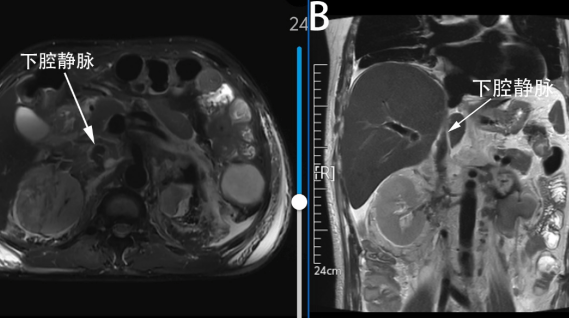

术后腹部MR平扫

术后闯关:从急性肾衰到顺利康复

术后,孙先生因术前肾功能受损及术中血管阻断时间较长,出现少尿型急性肾衰。在ICU团队的临时透析支持和精心护理下,他的尿量逐渐恢复正常,肾功能稳步回升。两周后,孙先生顺利转回普通病房,复查显示下腔静脉通畅,无癌栓残留,目前已康复出院,肌酐值接近正常水平。